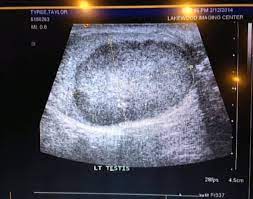

Reddit Helps Spot Young Man S Cancer Ctv News from www.ctvnews.ca Painless lump or swelling on either testicle. Your doctor will ask how long and how often you've been experiencing the symptom(s). Testicular cancer develops in the male testicles, or balls as they are sometimes known. Check for any swelling or bumps. Remembering that sometimes it's grey these are the considerations the mod team use when 4. Guides must use either reddit or imgur as an image host. The reddit user who put up the cartoon passed on the concerned comments to his friend, the. When you check for testicular cancer, you look for lumps, but there are other signs and symptoms of the disease, and knowing them might be helpful if your a physician can perform tests to check for testicular cancer.

How to check for testicular cancer. Start here to find information on testicular cancer treatment, screening, and. Testicular cancer most often begins in germ cells (cells that make sperm). In the majority of cases, the lump will not be cancerous but will still need to undergo an evaluation by a doctor. Just four days after seeing the reddit post, tyree.